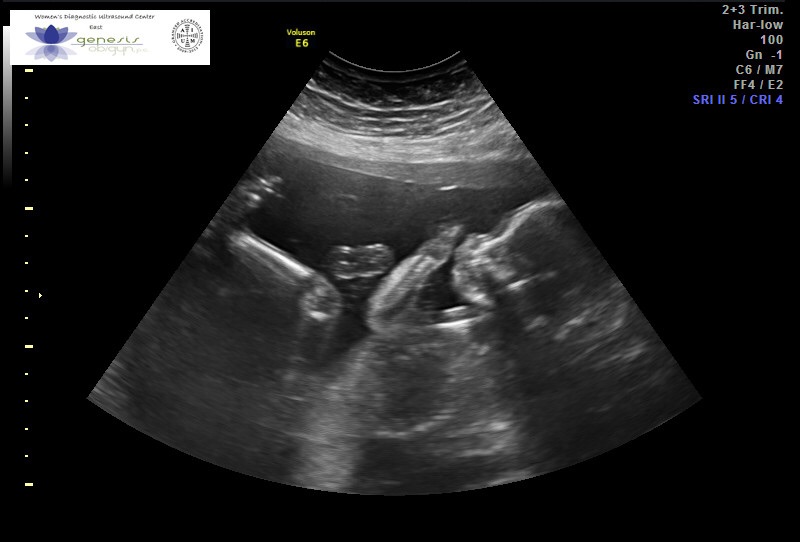

Anatomy Ultrasound Pics!